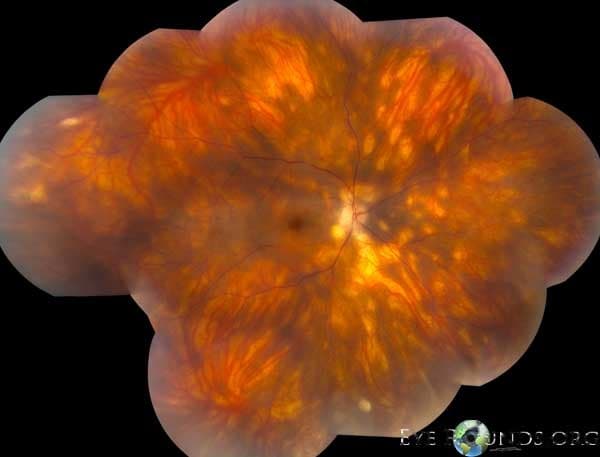

Clinical Images

High-resolution clinical photographs showing various presentations of floaters.